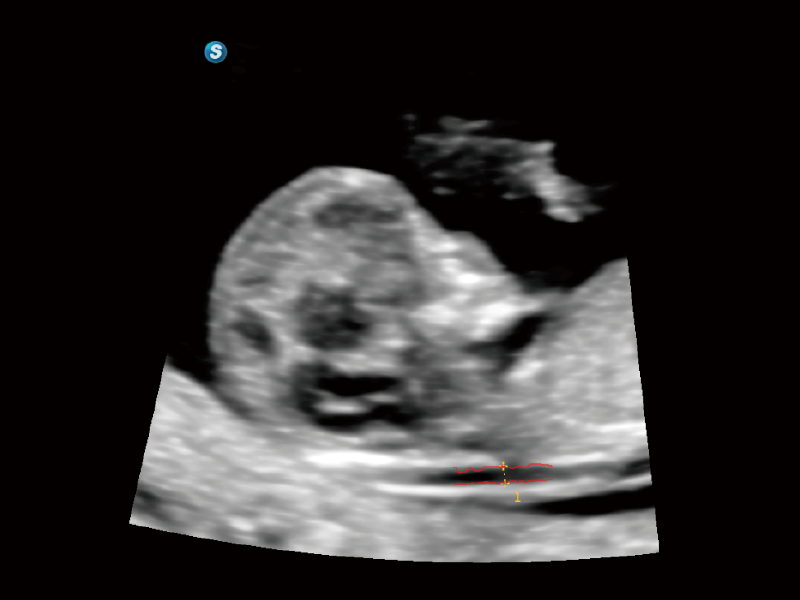

作為開立醫(yī)療全新打造的超高端旗艦超聲產(chǎn)品,從探頭抬起喚醒開啟掃查到多維探頭發(fā)射接收,通過先進(jìn)的場(chǎng)成像發(fā)射、自適應(yīng)聚合重建等技術(shù),基于RF Data原始射頻數(shù)據(jù)在圖像生成、高端功能等方面實(shí)現(xiàn)突破,為婦產(chǎn)科、兒科提供全方位臨床解決方案。

夢(mèng)溪?P80以“關(guān)愛女性”為基石,提供全方位的解決方案,量身定制以滿足女性的健康需求,涵蓋婦科、生殖健康檢查、產(chǎn)前篩查及產(chǎn)后康復(fù)等領(lǐng)域。